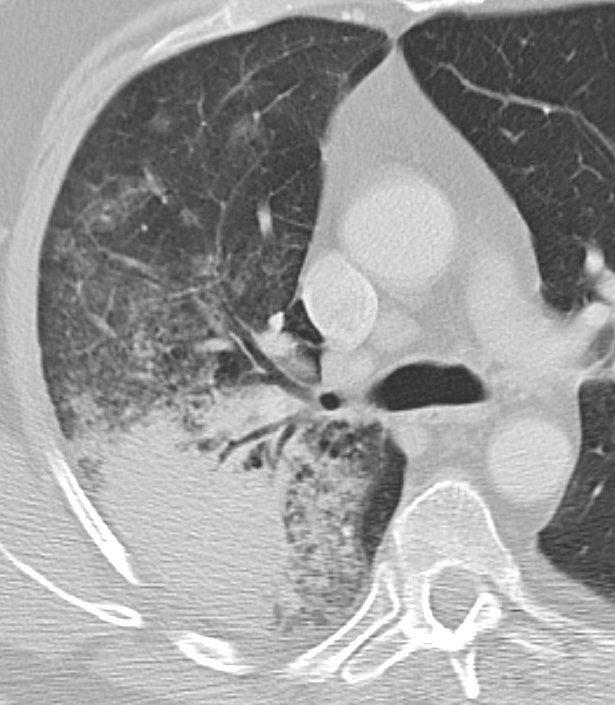

Gallery Lung Cancer BAC BAC Case 1 CTcu

BAC Case 1 CTcu